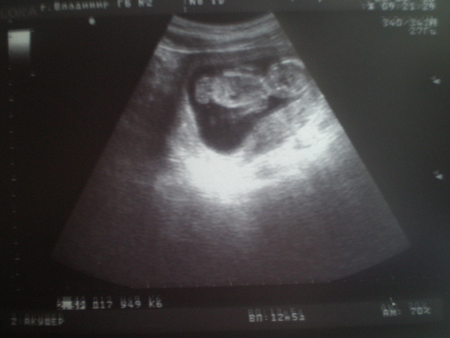

Ну а на фотках моё хулиганьё попой повернулось. Вот, смотрите

А вот результаты в цифрах:

CRL 3,8

BPD 2,4

AC 6,8

Ширина воротниковой зоны: 0,1 см

Сердцебиение: "+"

Движение: "+"

Плацентация по передней стенке.

Соответствуем сроку 13 недель.